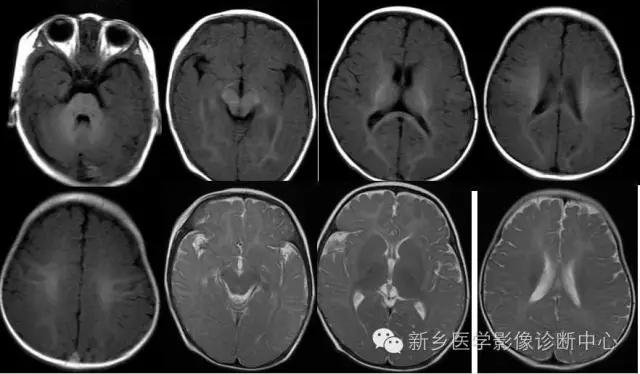

---I期:新生儿:出生至出生后1个月

髓鞘形成进程的MRI表现:

T1WI:高信号 T2WI:低信号

正常足月儿出生时:

放射冠中央

大脑脚、视束、桥脑、内囊后肢

丘脑腹外侧

小脑上蚓部、小脑上、下脚

---II期:早期婴儿阶段:出生后1~6个月

视放射、扣带回、禽距、小脑中部、小脑中脚、内囊前肢、胼胝体后部、膝部相继出现髓鞘形成。

---III期:后期婴儿阶段:出生后6~12个月

此时,白质内的水分逐渐下降,并有髓鞘形成,小脑半球、以至小脑叶、内囊全部、大脑枕叶、顶叶后部和额叶相继髓鞘形成和部分成熟。

---IV期:早期儿童阶段:出生后1~3年

>12个月~ 18个月 94% 属此期;

>18个月- <2岁100% 属此期。T2WI观察

亦称灰白质信号倒转期。随月龄增长大脑深部白质内水分降低,水分比灰质少,外围区皮质逐渐变薄,白质信号区逐渐扩大。此期中间区(白质)呈低信号,灰质与中央区呈中等信号。